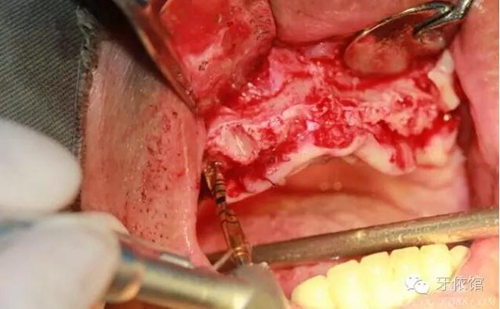

用擴(kuò)孔鉆去除切牙孔內(nèi)神經(jīng)纖維和血管

切牙壓孔內(nèi)植入植體,扭力50n